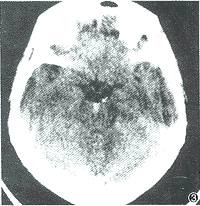

CT或MRI:CT或MRI扫描时直接提示脑水肿的最可靠诊断方法,CT图像所显示的征象,在病灶周围或白质区域,不同范围的低密度区,MRI在T1或T2加权像上,水肿区为高信号,较之CT扫描结果更确切。